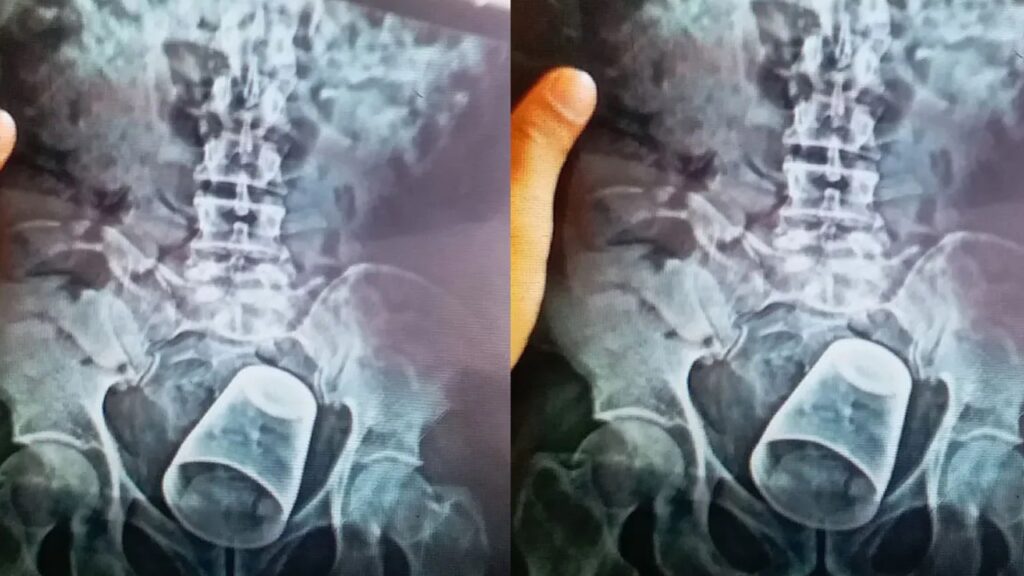

బిహార్ పాట్నాలోని పీఎంసీహెచ్ ఆస్పత్రిలో అరుదైన శస్త్రచికిత్స జరిగింది. ఓ వ్యక్తి ప్రైవేటు భాగాల్లో స్టీల్ గ్లాస్ ఇరుక్కుంది. ఈ షాకింగ్ ఘటన నవాదా జిల్లాలో వెలుగుచూసింది. ఓ వ్యక్తి మలద్వారంలోకి స్టీల్ గ్లాస్ చొచ్చుకెళ్లింది. దీంతో అతడు నొప్పితో విలవిల్లాడిపోయాడు. వెంటనే కుటుంబసభ్యులు అతడిని పాట్నాలోని పీఎంసీహెచ్ ఆస్పత్రికి తరలించారు. తొలుత కేసు వివరాలు తెలుసుకుని డాక్టర్లు ఆశ్చర్యానికి గురయ్యారు. ఆపై పరీక్షలు చేసిన డాక్టర్లు.. మలద్వారం నుంచి గ్లాసును వెనక్కి తీయడం సాధ్యం కాదని నిర్ధారించుకున్నారు. ఎక్స్రేలో కనిపిస్తున్న స్టీల్ గ్లాసుస్టీల్ గ్లాసు.. బాధితుడి మలద్వారంలో చాలా లోతుకు వెళ్లిందని వైద్యులు తెలిపారు. ఎక్స్రేలో ఈ విషయం స్పష్టంగా తెలిసిందని చెప్పారు.

ఆపై డాక్టర్ వినయ్ కుమార్ నేతృత్వంలోని ఐదుగురు సభ్యుల వైద్య బృందం విజయవంతంగా ఆపరేషన్ నిర్వహించింది. పొట్టకు ఆపరేషన్ నిర్వహించి గ్లాసును బయటకు తీశారు. ఆపరేషన్ పూర్తైన తర్వాత బాధితుడిని పర్యవేక్షణలో ఉంచారు. కొద్దిగంటల తర్వాత ఐసీయూ నుంచి సాధారణ వార్డుకు తరలించినట్లు వివరించారు. గ్లాసు అతడి రహస్య భాగంలోకి ఎలా వెళ్లిందన్న విషయంపై వైద్యులు అనుమానం వ్యక్తం చేస్తున్నారు. బాధితుడికి మతిస్థిమితం సరిగా లేదని బంధువులు చెబుతున్నప్పటికీ.. అతడు తమతో మామూలు వ్యక్తిలానే ప్రవర్తించాడని వైద్యులు పేర్కొన్నారు. స్టీల్ గ్లాసును బోర్లా వేసి దానిపై కూర్చున్నట్టు అతడు చెప్పినట్లు వెల్లడించారు. వైద్యులు ఈ విషయంపై పలు అనుమానాలు వ్యక్తం చేశారు. మంత్రతంత్రాలు, పూజలను సాధన చేసేందుకే అతను గ్లాస్పై కూర్చొని ఉంటాడని అనుమానిస్తున్నారు. ఈ క్రమంలోనే అది లోపలికి వెళ్లిపోయిందని చెబుతున్నారు.